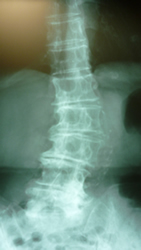

腰椎スベリ症(分離症)

腰椎4番がスベリ症です 長い間重量物の運搬と少し猫背が原因でしょうか、

年齢と共に多少のスベリ症患者は多く見受けられます。

過度の腰椎前弯を避けるよう指導し腰筋の柔軟性の腰痛体操を!